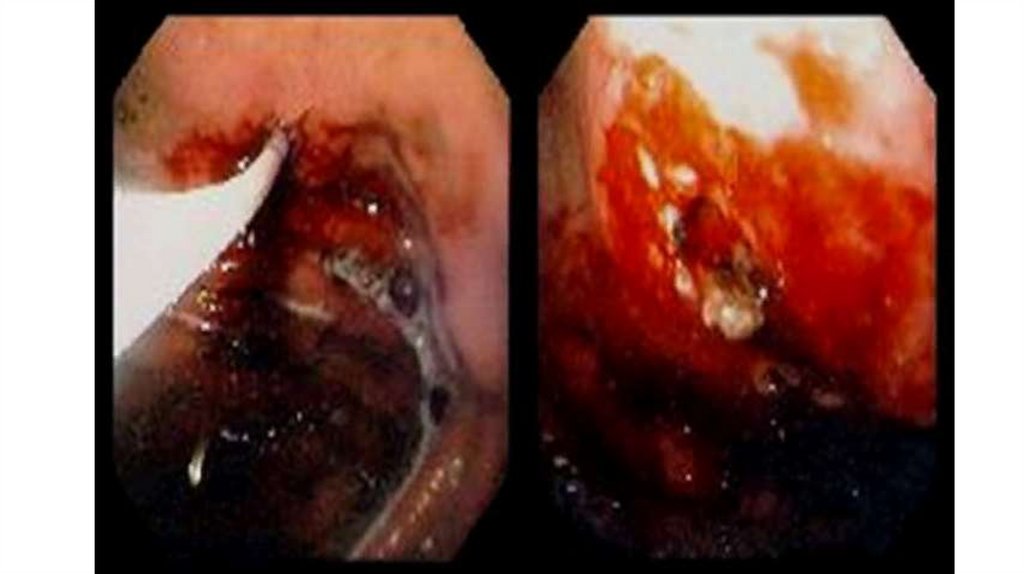

Эндоскопическое лечение

Для выполнения эндоскопического гемостаза и профилактики рецидива кровотечения

при ЯГДК рекомендуется применять следующие методы:

• механические (клипирование),

• термические (гидро-моно/би/мультиполярная, аргоно-плазменная коагуляция)

• инъекционные (склерозанты – полидоканол, этанол)

– в изолированном виде, либо в комбинации с инъекциями раствора адреналина.

Повторное контрольное эндоскопическое исследование / вмешательство

рекомендуется выполнить при неполноценном первичном осмотре/гемостазе и у

пациентов с высоким риском рецидива кровотечения.

При рецидиве кровотечения в стационаре в большинстве случаев рекомендуется

выполнение повторного эндоскопического гемостаза.